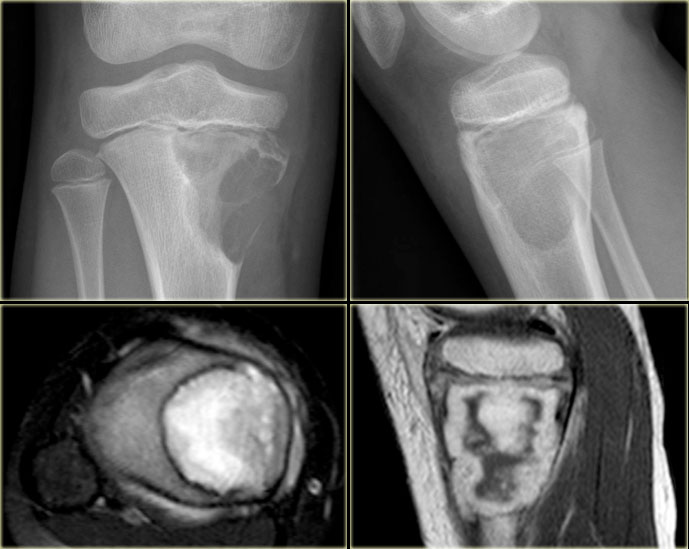

GCT in distal femur GCT in distal femur

Giant cell tumor (2)

On the left a giant cell tumor presenting as an eccentric lytic lesion in the medial epi- and metaphysis of the distal femur.

There is a small transitional zone resulting in well-defined borders.

Continue with the MR-images.

Giant cell tumor (2) continued

MR-images of the same patient.

Sagittal T1-weighted TSE images before and after Gd.

The tumor extends to the subchondral bone plate with endosteal cortical involvement.

There is inhomogeneous enhancement.

On T2-weighted image, the tumor has a remarkable low SI, which is commonly seen in GCT.

There is surrounding edema with high SI.